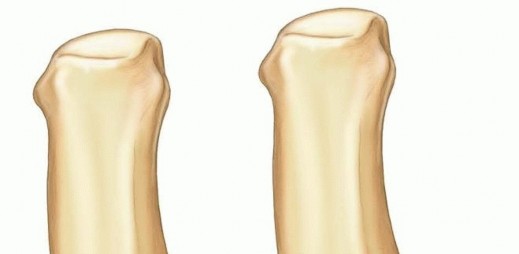

Osteology and Articular Kinematics

The osseous architecture of the thumb CMC joint is inherently unstable without its soft tissue envelope. The articular surface of the trapezium is saddle-shaped, articulating with the reciprocally shaped base of the first metacarpal. During palmar abduction, the metacarpal base glides dorsally on the trapezium, while during adduction, it glides volarly. Flexion and extension involve a complex rolling and gliding mechanism along the orthogonal axis. This intricate kinematic dance means that any articular step-off greater than 1 millimeter will drastically alter contact pressures, leading to point loading, accelerated cartilage wear, and inevitable early-onset osteoarthritis.